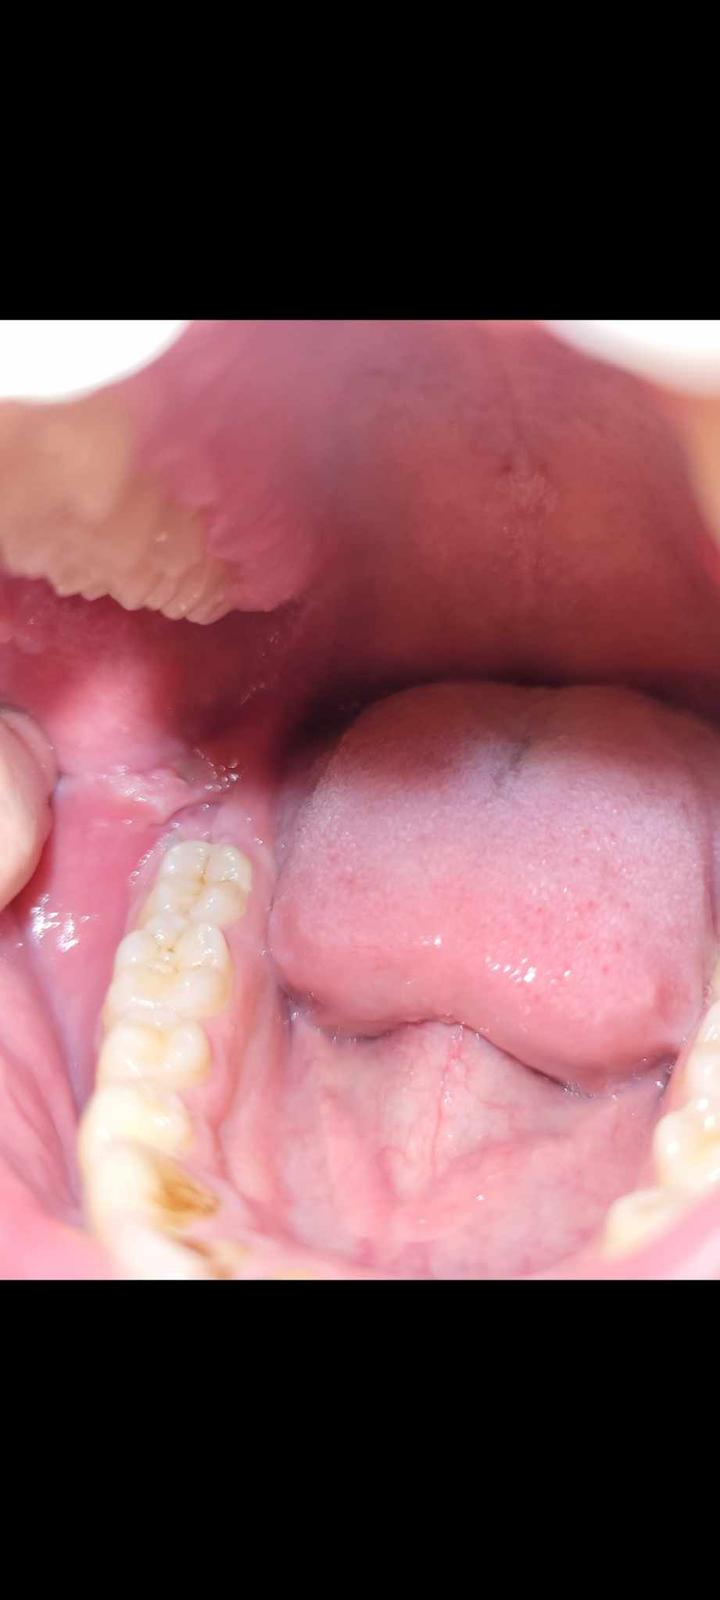

Čo spôsobuje opuch na líci vľavo?

@lilyianka Ked si to z prstom trošku pohnem tak vnutri to je ako keby otvorene na 2 polovice , neviem to lepšie vysvetlit ..... celkom sa bojim

Mas poskodenu sliznicu a dostali sa ti tam bakterie z ust, tak sa ti to zapalilo. Nieco ako afta.

A mas zubny kamen na prednych zuboch zvnutra. V tom sa drzia bakterie (plus si zarabas na odhalene krcky zubov). Daj si ho vycistit na zubnej hygiene.

Mne to príde ako keď si zakusneš zubami do líca.